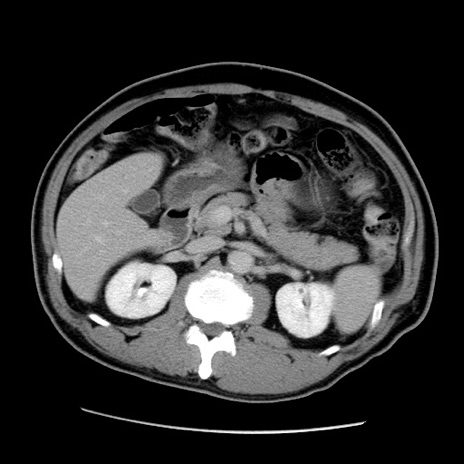

症例22(横断像)

【症例】50歳代男性

【主訴】腹痛

【現病歴】AVMからの被殻出血のため回復期リハ病棟入院中。 本日午後3時頃急に下腹部痛が出現した。

【既往歴】AVM、被殻出血、虫垂炎、高血圧

【身体所見】意識晴明、左半身不全麻痺、会話の理解は良好、36.5°C、腹部:膨隆、全体に板状硬、下腹部正中に圧痛点あり、反跳痛-、筋性防御不明、右下腹部にope scar

【データ】WBC 9400、CRP 0.06